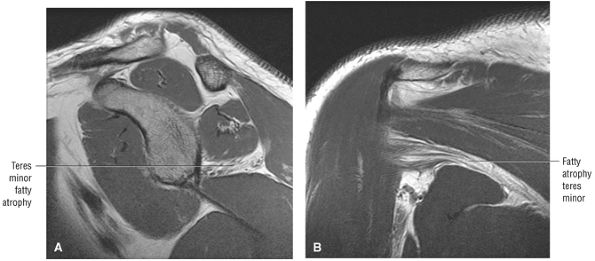

FIGURE 8.102 ● (A) The anterior undersurface of the acromion and the coracoacromial ligament form the coracoacromial arch. The subacromial subdeltoid bursa facilitates the passage of the rotator cuff and proximal humerus under the coracoacromial arch. (B) A superior axial image shows the anterior-to-posterior extent of the coracoacromial (CA) ligament perpendicular to the supraspinatus tendon. The fluid in the subacromial-subdeltoid bursa represents fluid between two serosal surfaces in contact with each other. One serosal surface is contributed by the undersurface of the coracoacromial arch and deltoid, and the other serosal surface is on the bursal side of the cuff.

|

![]() |

FIGURE 8.103 ● Pseudospur. The normal broad attachment of the coracoacromial ligament to the inferior surface of the acromion is shown on (A) T1-weighted coronal oblique and (B) sagittal oblique images. The low-signal-intensity acromial cortex (black arrows) and adjacent coracoacromial ligament and lateral slip of the deltoid attachment (white arrows) give the false impression of a small subacromial spur in the coronal plane. This pseudospur should not be misinterpreted as impingement; otherwise, unnecessary acromioplasties may be performed on patients with a normal coracoacromial ligament attachment and no associated acromial spurs.